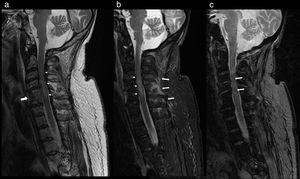

Cervical CT scan: no vertebral alignment disruption. Fusion of C5–C6 vertebral bodies. Spinous process fractures of C6 and C7. Cervical arthritis. No soft tissue masses (Fig. 1).

Figure 1.Cervical CT study on sagittal (a) and axial (b) planes. Hypoplasia of the vertebral bodies C5 and C6 with “wasp waist” typical of congenital fusion, with fusion of the facet joints, without fusion of the spinous processes is shown. Anterior osteophytes identified, mainly in the bodies adjacent to the vertebral fusion and rectification of the lordosis, conditioning a canal stenosis in C3 and C4. A discrete subluxation of C2 on C3 is observed, without associated atlantoaxial or atlanto-occipital subluxation, or hypoplasia of the atlas or odontoid hypoplasia. Undisplaced fractures in the C5, C6 and C7 spinous processes (arrows).